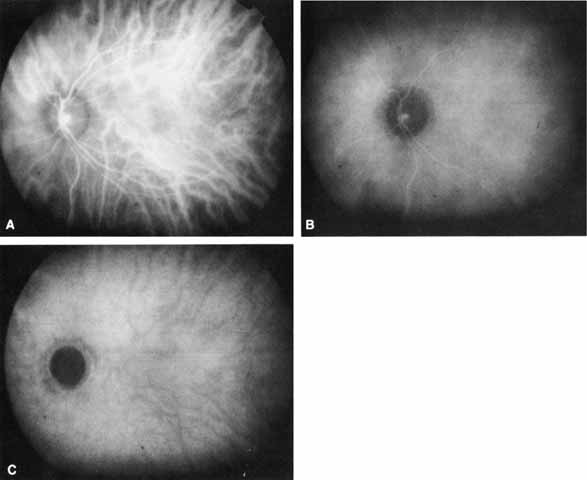

The “early” phase (0–3 minutes after injection) encompasses the period from the first appearance of ICG dye in the choroidal arterial circulation to the point of maximal ICG choroidal hyperfluorescence, usually occurring within the first minute after the injection of dye (Fig. 1A). During this phase, both medium and large choroidal arteries and veins are well visualized beneath the hyperfluorescent retinal vasculature. Individual choriocapillaris vessels cannot be distinguished. The areas surrounding middle and large choroidal vessels appear relatively hypofluorescent. This “pseudohypofluorescence” is, at least in part, a result of a smaller volume of blood in the choriocapillaris compared with the larger vessels, with the illumination intensity adjusted for the strongest portion of fluorescence.

Fig. 1 Normal Indocyanine Green (ICG) angiogram. A. Early phase photograph (90 seconds after dye injection) shows the hyperfluorescent choroidal and retinal vessels. B. Middle-phase photograph (10 minutes after dye injection) reveals more homogeneous background choroidal fluorescence with relative attenuation of the retinal vascular fluorescence. C. Late-phase photograph (30 minutes after dye injection) shows medium-sized choroidal vessels in relief (relative hypofluorescence). No retinal structures are visible.

In the “middle” phase of the angiogram (5–15 minutes after injection), the choroidal veins become less distinct as a nearly homogeneous, diffuse choroidal fluorescence emerges (see Fig. 1B). The fluorescence from the retinal vessels also begins to attenuate. Lesions that demonstrate abnormal hyperfluorescence on ICGA typically begin to stand out in contrast to the fading surrounding normal background fluorescence by this point in the study.

In the “late” phases (beyond 18–22 minutes), all details of normal retinal and choroidal vessels are lost as the hyperfluorescence fades even further (see Fig. 1C). The choroidal vessels now stand out in relief as hypofluorescent channels and retinal vessels are no longer visible, and the optic nerve head is dark. There is maximal contrast with any abnormal hyperfluorescent lesions. The edges of such lesions may exhibit some “fuzziness” at this stage, apparently from limited dye leakage.